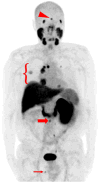

Methods: Five patients with known metastatic RCC were imaged with the low-molecular weight radiotracer ¹⁸F-DCFPyL, an inhibitor of the prostate-specific membrane antigen at 60 min post injection. ¹⁸F-DCFPyL PET/CT and conventional images (either contrast-enhanced computed tomography or magnetic resonance imaging) were centrally reviewed for suspected sites of disease.

Results: In all five patients imaged, sites of putative metastatic disease were readily identifiable by abnormal ¹⁸F-DCFPyL uptake, with overall more lesions detected than on conventional imaging. These PET-detected sites included lymph nodes, pancreatic parenchymal lesions, lung parenchymal lesions, a brain parenchymal lesion, and other soft tissue sites. ¹⁸F-DCFPyL uptake ranged from subtle to intense with maximum standardized uptake values (SUVmax) for the identified lesions of 1.6-19.3. Based upon this small patient series, limited pathology and imaging follow-up of these patients suggests a higher sensitivity for ¹⁸F-DCFPyL compared to conventional imaging in the detection of metastatic RCC (94.7 versus 78.9%).

Conclusions: PSMA expression in the tumor neovasculature of RCC has been previously established and is believed to provide the basis for the imaging findings presented here. PSMA-based PET/CT with radiotracers such as ¹⁸F-DCFPyL may allow more accurate staging of patients with RCC and conceivably the ability to predict and follow therapy in patients treated with agents targeting the neovasculature.